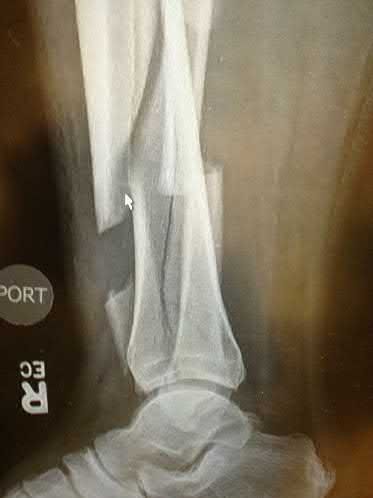

A 25-year-old female is involved in a motor vehicle collision. She presents with the isolated injury seen in Figures A through D. Her leg is swollen but her skin is intact. She has no clinical signs of compartment syndrome. Which of the following treatment options will allow for maintenance of fracture alignment and minimize the risk of soft tissue complications?

The patient presents with a closed distal third metaphyseal-diaphyseal distal tibia fracture with simple intra-articular extension. Immediate intramedullary nailing along with percutaneous fixation of the articular component provides appropriate restoration of length, rotation and alignment and minimizes the risk of wound complication.

Displaced distal third tibia fractures may be associated with simple intraarticular extension. Operative treatment of intra-articular distal tibia fractures has historically been performed with open reduction and internal fixation. Early open reduction and plate fixation of pilon fractures has been associated with high rates of infection and wound complication. In select patterns with simple articular extension, percutaneous screw fixation and medullary nailing may provide appropriate reduction with minimal soft-tissue risk.

Figures A and B demonstrate a distal third tibial shaft fracture with simple intra-articular extension. The axial and coronal CT cuts in Figures C and D further clarify the articular injury. Illustrations A and B demonstrate a comminuted distal third tibial fracture with simple intra-articular extension. Illustrations C and D are fluoroscopic images of the same injury after intramedullary nailing and percutaneous fixation of the articular component.